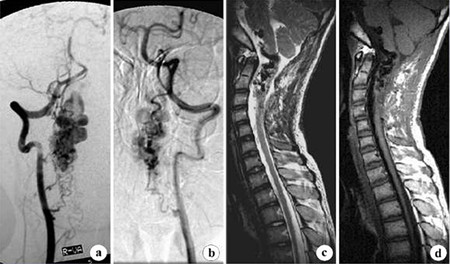

这些病变通常需要做专业检查诊断,对具有波动性症状的病人进行连续磁共振扫描,病变的体积可能有所变化,脊髓造影和血管造影很少有异常,通常不能做出海绵状血管畸形的诊断,有时有必要行脊髓血管造影,对海绵状血管畸形与其他类型的血管畸形区别。

DSA即血管造影的影像通过数字化处理,把不需要的组织影像删除掉,只保留血管影像,这种技术叫......>>详细